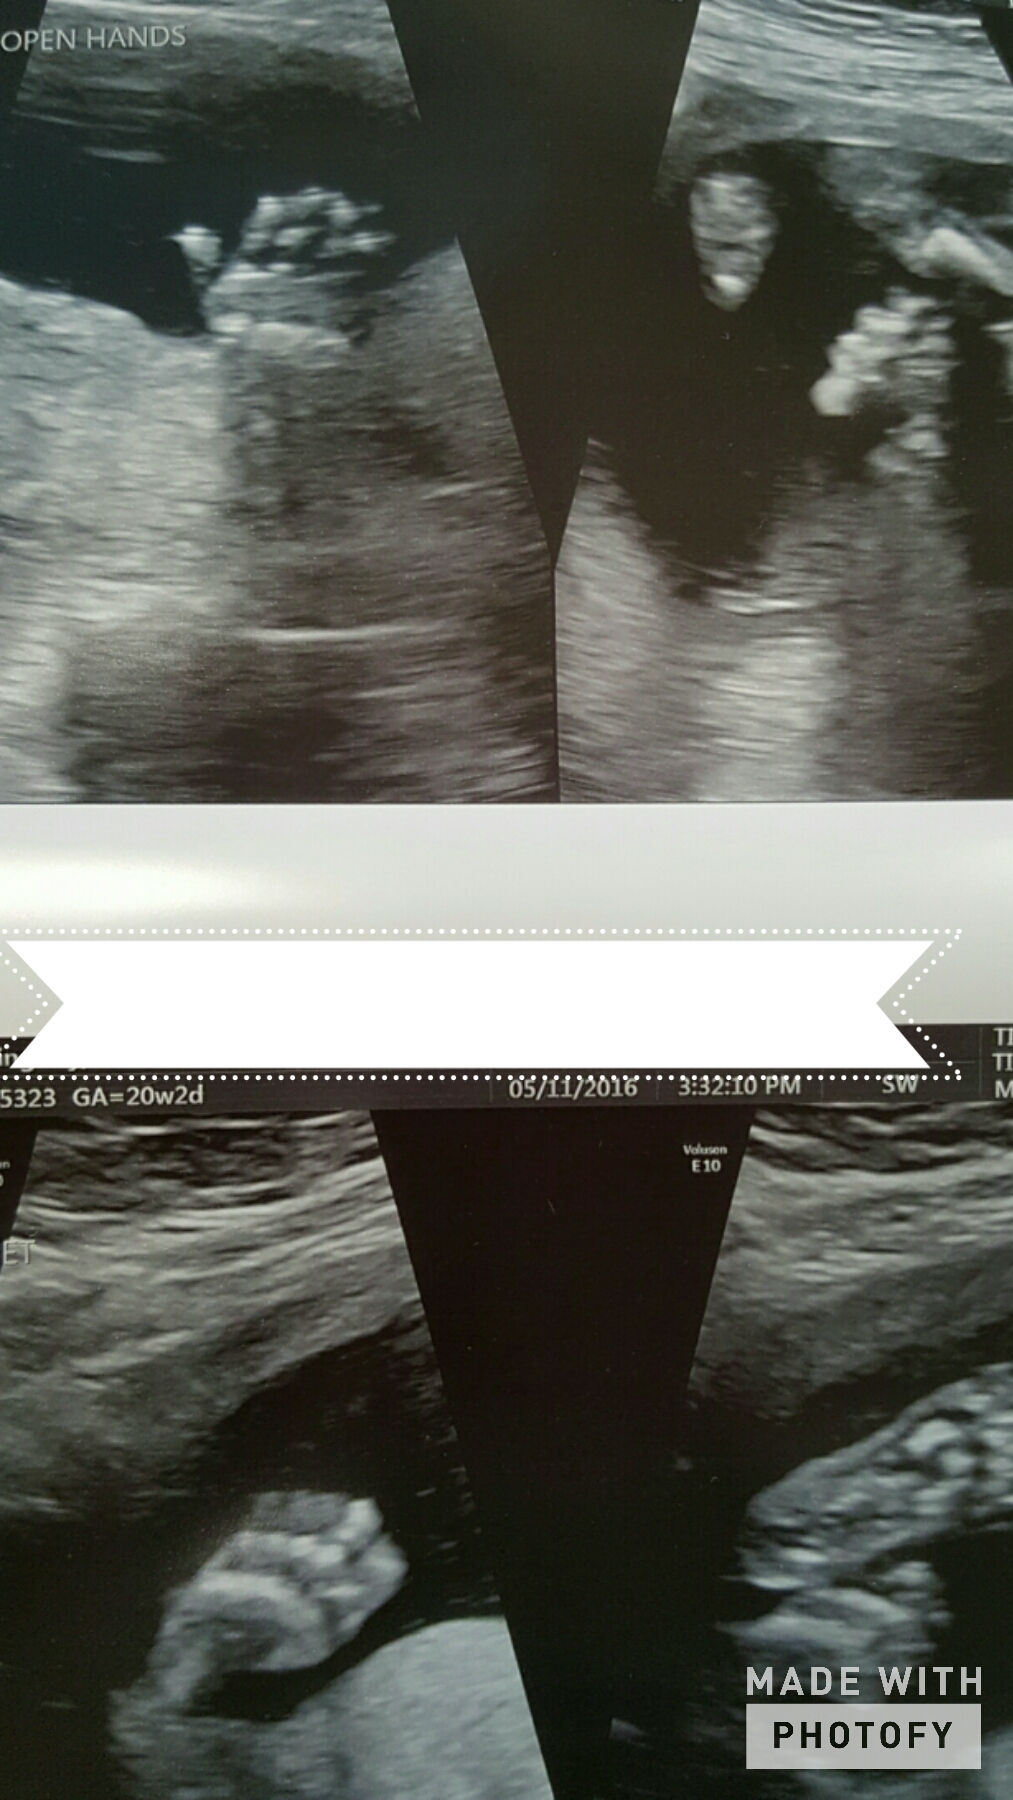

Had my anatomy scan today. She's measuring a little on the small side, 9 oz at 19w 5 d, which they said is in the 12th percentile, but otherwise she's doing great!

Baby girl at 27.3. She kept her hands and feet in front of her face the whole time, we even saw her sucking on her toe. Can't wait to meet this little one!